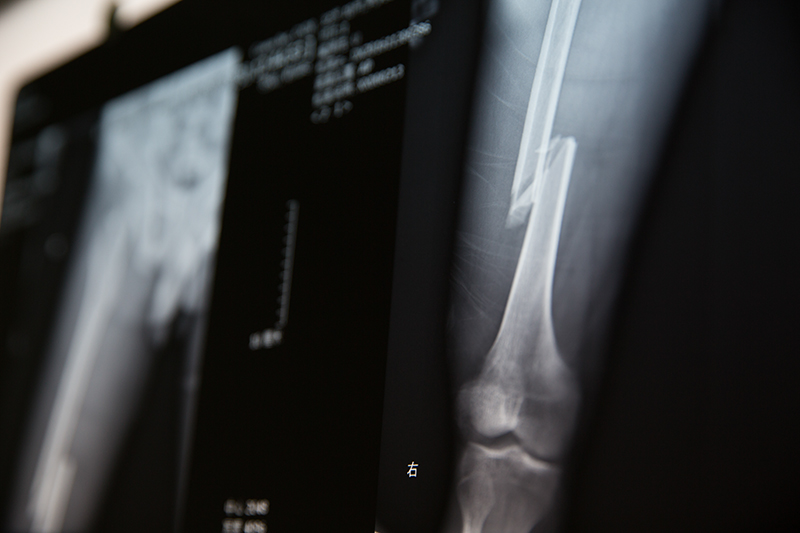

X光片显示,患者为右腿股骨骨折,手术方案为闭合复位微创髓内固定。为了不破坏骨折端的血供,利于骨折更早、更好地愈合,对骨折断端不切开、不显露,完全依靠透视,对骨折进行复位和固定。

骨折复位是个精细活儿,王红川主任和助手需要通过实时的X光影像为患者实施精准复位。而此时医生则完全暴露在X光机前,接受着X射线的一次又一次“洗礼”......